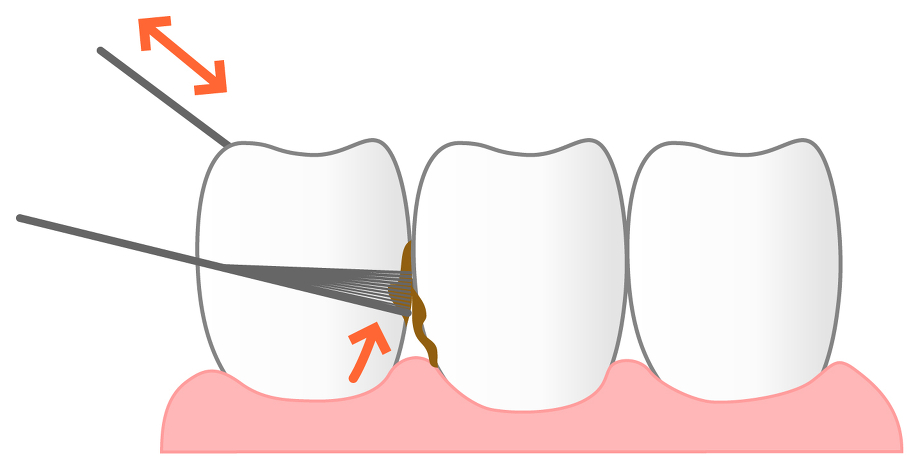

⑥ 前回詰めた綿花の状態を確認して、良い状態なら、「根管充填剤」(マスターポイント・アクセサリーポイント)というお薬を、余分な空間がないように根っこに詰めます。

⑥ 前回詰めた綿花の状態を確認して、良い状態なら、「根管充填剤」(マスターポイント・アクセサリーポイント)というお薬を、余分な空間がないように根っこに詰めます。 Q1.痛みはありますか?

Q1.痛みはありますか? ② 次に、「根管長測定器」という機械を使い、根っこの長さを正確に測ります。

② 次に、「根管長測定器」という機械を使い、根っこの長さを正確に測ります。